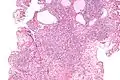

| Micrograph of a nephrogenic adenoma. H&E stain. | |

Nephrogenic adenomas are diagnosed under the microscope by pathologists. Microscopically the tumor shows closely packed small tubular structures in edematous stroma. The tubules show considerable variation in size and shape resembling convoluted tubules of the kidney. The single layer of cells lining the tubules are cuboidal with a scant to moderate amount of cytoplasm. In some areas they may have a hobnail appearance. [2]